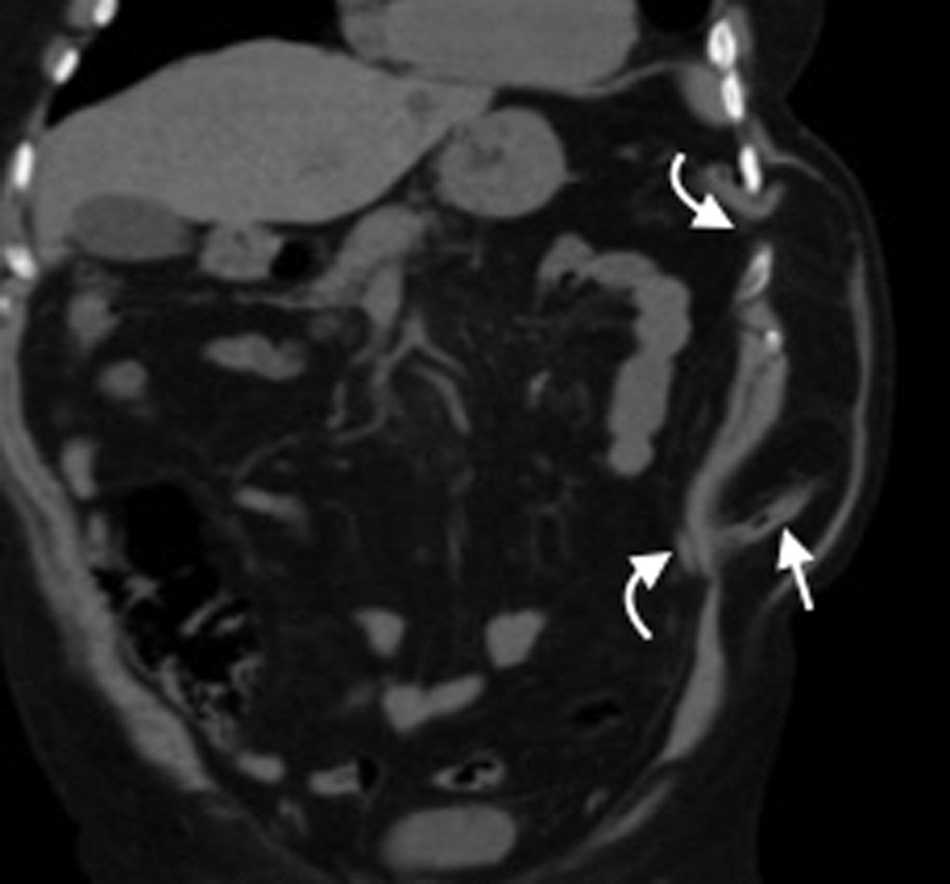

Hernia femoral

Menos frecuente que la inguinal, esta se produce cuando el contenido peritoneal penetra el canal femoral junto con la arteria y la vena femoral4. Esta región tiene una configuración más sencilla que el canal inguinal, se forma con el ligamento inguinal hacia arriba, el borde medial del m??sculo aductor hacia dentro, el m??sculo sartorio hacia afuera y los m??sculos psoas il??aco, pect??neo y el aductor largo haciendo de piso8. La principal característica del triángulo es la vaina femoral, que es una condensaci??n de la fascia profunda (fascia lata) del muslo y contiene, en direcci??n lateral-medial, a la arteria, la vena y el canal femoral1. Es más frecuente en mujeres y del lado derecho4.

En la TCMD el cuello del saco herniario se identifica como una estrecha protrusi??n a trav??s del anillo femoral, en direcci??n caudal al origen de los vasos epig??stricos inferiores y de forma medial a la vena femoral com??n, que frecuentemente aparece comprimida por el saco herniario (fig. 3). A veces en la evaluaci??n cl??nica resulta dif??cil distinguir una hernia femoral de una inguinal, por lo que la TCMD tiene un rol importante en su diferenciaci??n y valoraci??n del contenido2. Lo m??s com??n es visualizar asas de intestino delgado dentro del saco herniario, pero tambi??n se puede encontrar el ap??ndice dentro de este canal. Esto ??ltimo es poco frecuente (1% de los casos) y recibe el nombre de hernia De Garengeot9 (tabla 2).